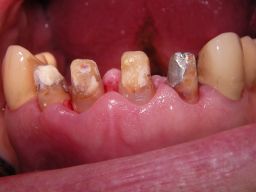

Weil auch die anderen Schneidezahnkronen (12-22) durch Randreparaturen und den schlechten Randschluß erneuerungsbedürftig aussahen, wurden 4 Einzelkronen geplant. Vorher hieß es aber noch, die schlechte Wurzelfüllung im Zahn 12 (Röntgenbild links) besser zu machen. Hierfür wurden am 17.2.06 die alten Kronen 11 und 12 entfernt. Rechts das Bild nach Entfernung von alten Füllungen und Karies. | |